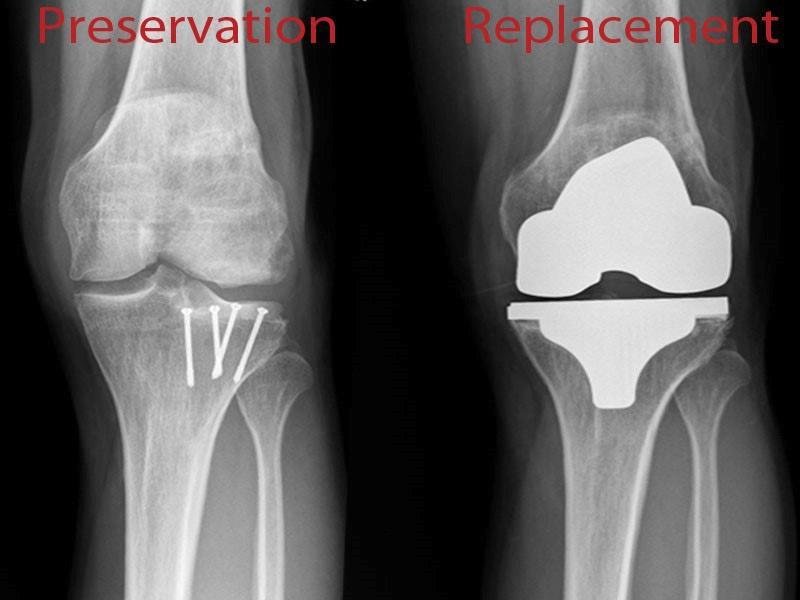

Knee preservation surgery encompasses a range of surgical techniques aimed at treating knee joint conditions, particularly osteoarthritis, in a way that maintains as much of the natural knee structure as possible. These surgeries are designed to alleviate pain, improve function, and delay the need for more invasive procedures like total knee replacement. Minimally invasive surgery using a small camera (arthroscope) and instruments inserted through tiny incisions. Typically quicker than open surgery, with patients often resuming normal activities within weeks. Cutting and realigning the bones to redistribute weight and relieve pressure on the affected knee compartment. Harvesting and culturing cartilage cells from the patient, then re-implanting them into the defect. Transferring healthy cartilage and bone from one area of the knee to the damaged area. Generally quicker and less painful than total knee replacement, with many patients returning to normal activities within a few months. Knee preservation surgeries can be highly effective for the right patients, particularly those who are younger and more active, providing a means to manage knee problems while maintaining natural joint integrity for as long as possible.